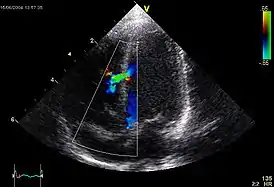

![]() Эхокардиографическое изображение дефекта межелудочковой перегородки в мышечной части. | |

При допплер-ЭхоКГ уточняется место расположения дефекта, его размер, определяется давление в правом желудочке и лёгочной артерии. В первой стадии лёгочной гипертензии давление в ПЖ не превышает 30 мм.рт.ст., во второй стадии — от 30 до 70 мм.рт.ст., в третьей — более 70 мм.рт.ст.[6]